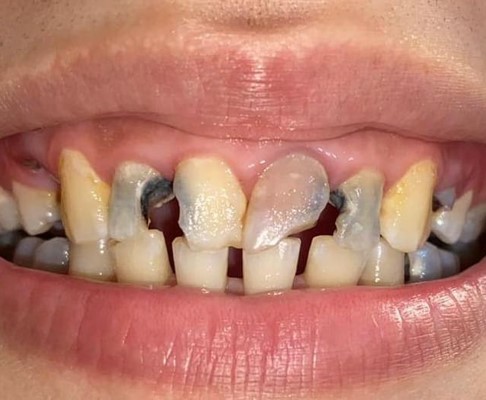

Endodontics

Before After

Before

After

Root canal treatment with crown restoration